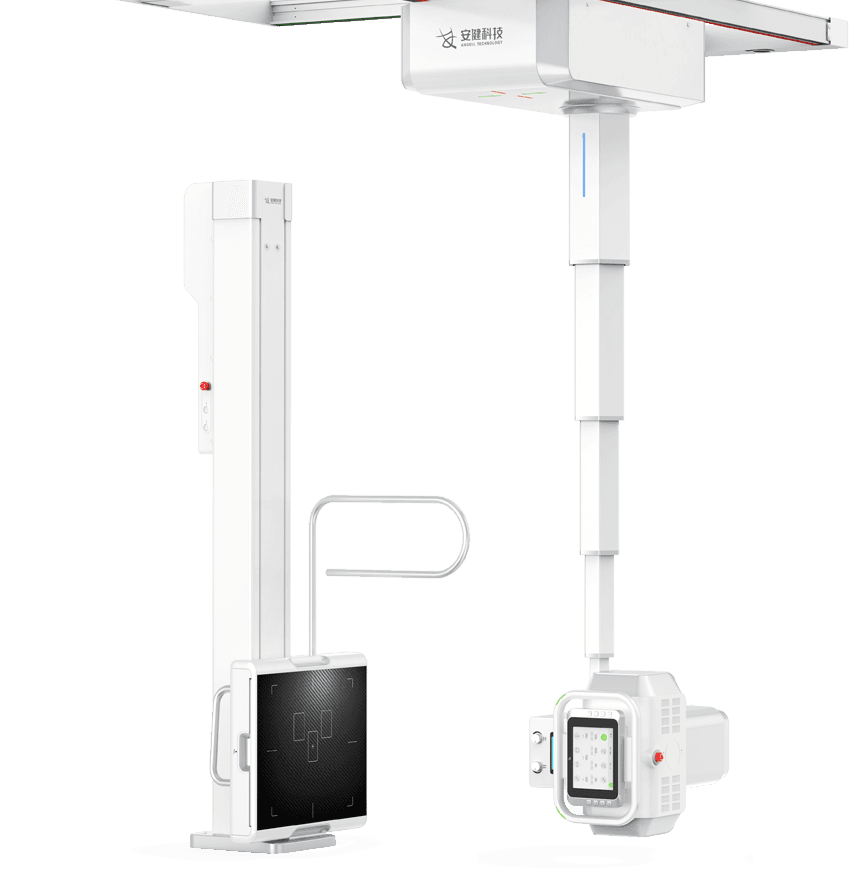

ЧрБъїК±ИЛЙъѕНКЗІ©їЖјјЧФЦчСР·ўµД¶ЇМ¬МЅІвЖчјјКхЈ¬ИГБЩґІјмІйѕЯ±ёїЙКУ»ЇМхјюЈ¬ІўКµПЦїмЛЩёЯЗеµгЖ¬Ј¬

ѕ«ЧјІ¶ЧЅІЎФоЎЈКµПЦґУ¶юО¬ЅвЖКіЙПсµЅЖч№Щ№¦ДЬіЙПсЧЄ±дЈ¬ИГХп¶Пёьѕ«ЧјЎЈ

ёЯЗе¶ЇМ¬

ЖЅ°еМЅІвЖч

4DК®ЦбБЄ¶ЇФЛ¶ЇПµНі

¶а№¦ДЬРьµхКЅ»ъРµФЛ¶ЇЈ¬И«ЖЅєвОИ¶ЁРФЙијЖЈ¬4DК®ЦбБЄ¶ЇјјКхЈ¬»ъјЬФЛ¶ЇЧФИзЖЅОИЈ¬

ЕдєПµз¶ЇЙэЅµґІј°¶а№¦ДЬБўКЅЙгУ°јЬЈ¬ЗбЛЙВъЧгБЩґІИ«МеО»ЙгУ°РиЗуЎЈ

Зт№ЬОеПтКЦЧФТ»МеФЛ¶Ї

ІЙУГКЦ¶ЇУлµз¶ЇТ»Ме»ЇЙијЖЈ¬ІўѕЯ±ёёРУ¦Зэ¶Ї№¦ДЬЈ¬

Т»јьЅвЛшјґїЙЗбЛЙІЩїШЗт№ЬµДИ«ПтФЛ¶ЇЎЈ -

МЅІвЖчЎўЗт№ЬЛ«ПтЧФ¶ЇёъЧЩ

МЅІвЖчУлЗт№ЬїЙКµПЦЛ«ПтЧФ¶ЇёъЧЩЈ¬

БўОФО»ёЯѕ«¶ИКµК±Н¬ІЅЈ¬ґу·щМбёЯБЩґІјмІйР§ВКЎЈ -

И«ЧФ¶Їі¤№ЗЖґЅУ

Т»јьКЅЖґЅУЙгУ°ЕДЙгіМРтЈ¬їмЛЩЅшРР·Ц¶ОЙгУ°Ј¬єуМЁ

ЧФ¶Їґ¦АнЖґЅУУ°ПсЈ¬К№ЖґЅУіЙПсёЯР§ѕ«ЧјЎЈ -

БўОФО»Т»јьЗР»»ЎўЎЄјьµЅО»

И«ЧФ¶ЇЦЗДЬФЛ¶ЇїШЦЖЈ¬ЙдЖµРЕєЕЛ«ПтЅУКХЙијЖЈ¬

КµПЦБўОФО»Т»јьЗР»»ЎўТ»јьµЅО»Ј¬јт»ЇІЩЧчЈ¬МбЙэР§ВКЎЈ -

µз¶ЇЙэЅµґІ

і¬ґуРРіМФЛ¶Ї·¶О§Ј¬Бй»оУ¦¶Ф¶щНЇЎўАПИЛЎўНвЙЛ»јХЯЙППВґІЎЈ

Ед±ёЗ¶ИлКЅёРУ¦ЅвЛшПµНіЈ¬ЗбЛЙµчЅЪґІёЯІўУРР§±ЬГв»јХЯО󴥡Ј

ёЯС№·ўЙъЖч

УЕЦКЎўОИ¶ЁЙдПЯКдіцЈ¬ВъЧгґу№жДЈБ¬РшЕДЙгРиЗуЈ¬і¤К±јдФЛРРІ»еґ»ъЎЈ -

ёЯИИИЭБїЗт№Ь

УЕЦКЎўОИ¶ЁЙдПЯКдіцЈ¬ВъЧгґу№жДЈБ¬РшЕДЙгРиЗуЈ¬і¤К±јдФЛРРІ»еґ»ъЎЈ -

ЖЅ°еМЅІвЖч

З§Нтј¶ПсЛШОЮПЯЖЅ°еМЅІвЖчЈ¬ЦЗДЬФЪПЯідµз -